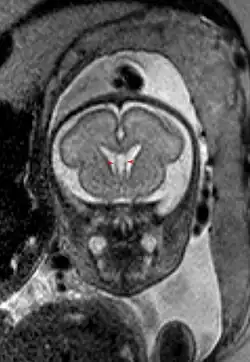

Cavum septi pellucidi

Als Cavum septi pellucidi (auch Septum-pellucidum-Zyste, Pseudoventrikel, fünfter Ventrikel, Duncans Ventrikel, Sylvischer Ventrikel, Vieussens’ Ventrikel, Wenzels Ventrikel und weitere) bezeichnet man den Hohlraum zwischen den Blättern des Septum pellucidum zwischen den Vorderhörnern der Seitenventrikel des Gehirns. Wenn eine Ausdehnung nach dorsal hinter das Foramen Monroi vorliegt, spricht man von einem Cavum vergae, wobei es sich nicht um eine andere anatomische Struktur handelt.

Der Hohlraum beinhaltet in der Regel normalen Liquor. Eine Kommunikation mit den anderen Liquorräumen kann, muss aber nicht vorhanden sein. Als Zufallsbefund beim Erwachsenen in der Computertomographie oder Kernspintomographie gefunden, ist das Cavum meist nur wenige Millimeter groß. Auch größere Befunde machen selten Probleme. In Einzelfällen kommt es zu einer Kompression des Foramen Monroi mit Ausbildung eines Hydrozephalus. In diesen Fällen ist eine neurochirurgische Behandlung zur Dekompression notwendig.